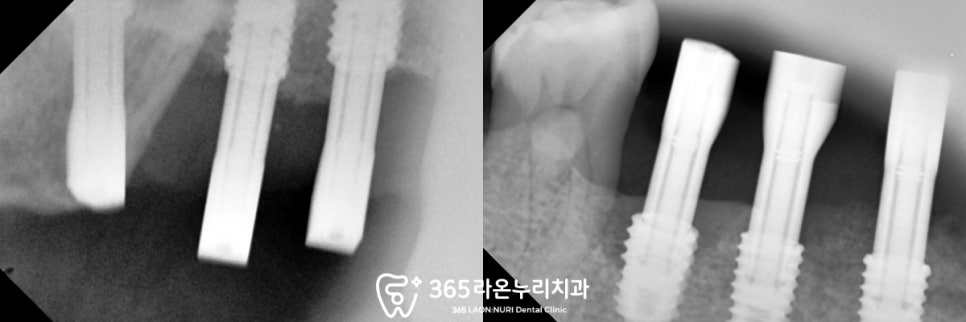

▮ 3. 오른쪽 위아래 식립

오른쪽 위 어금니부터

순차적으로 식립을 진행하는 모습입니다.

치조골이 녹아 흔들리는 이는 빼고

그 자리에 임플란트와 골이식을

동시에 해드렸는데요,

위 어금니 부근에는

상악동이라는 해부학 구조가 있어

심는 과정에서 천공이 생기지 않도록

주의하였습니다.

아래쪽도 마찬가지로

하치조신경 및 이공의 위치를

미리 예측하여

안전한 거리에 심어드렸으며